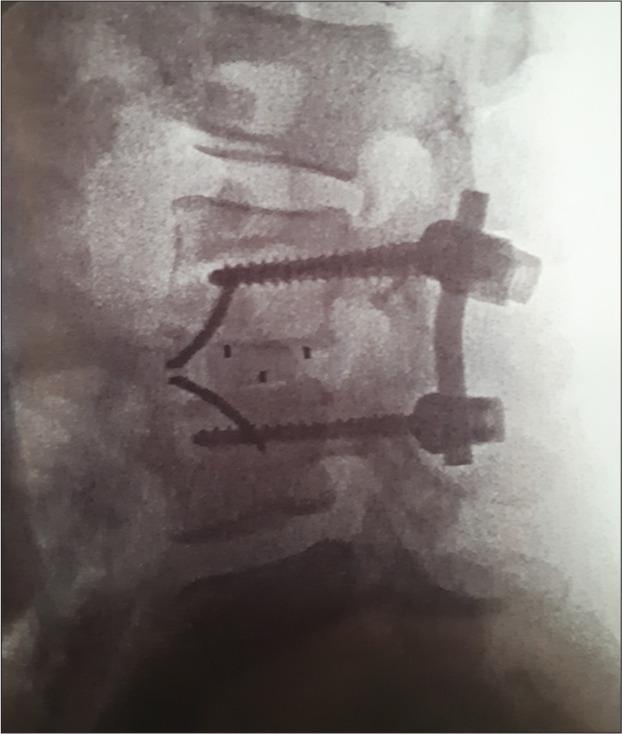

A 46-year-old female underwent a TLIF L3-L4. Five months later, she presented with cauda symptoms/signs of dorsal cage migration that warranted surgical removal.

TLIF can be associated with delayed dorsal cage migration into the spinal canal. This adverse event should be clinically recognized, radiologically documented, and appropriately surgically treated to minimize short/long-term neurological sequelae.

一名46岁女性接受了L3-L4节段的TLIF手术。五个月后,她出现了融合器向后移位至椎管的马尾症状/体征,需要进行手术取出。

TLIF可能与融合器延迟向后移位至椎管有关。这种不良事件应在临床上得到认识,通过放射学记录,并进行适当的手术治疗,以尽量减少短期/长期神经后遗症。